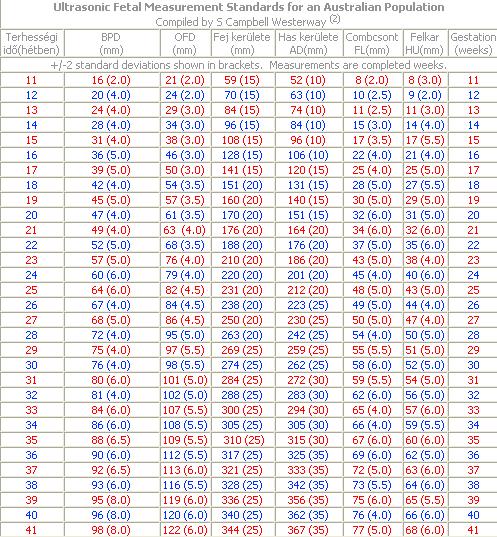

Ha nagyon uncsizol a szulesvarakozasban, tegyel fel nekem legyszi egy tablazatot az UH kifejezesekrol, roviditesekrol, meretekrol. Koszonom